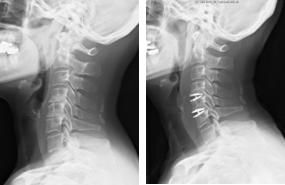

頚椎前方固定術

対象となる疾患は、頚椎症性脊髄症、頚椎症性神経根症、頚椎後縦靭帯骨化症、頚椎椎間板ヘルニア、脊椎・脊髄腫瘍などです。前方から圧迫因子となっている椎間板や骨を取り除き、代わりに腸骨などの自家骨や人工骨、もしくはスペーサーなどを挿入して、障害部位の可動性を止めることで神経症状の改善が見込まれます。前方からの圧迫因子が大きい場合、不安定性がある場合、後弯と言って骨の並びが後ろに弯曲している場合には有効な手術法となります。近年では、金属製のプレートとスクリューなどで早期離床が可能となっており、通常、手術翌日より座位や歩行訓練を行います。術後は、頚部を固定する装具を約1−3カ月装着します。

-

手術前のMRIでは、第6/7椎間の椎間板が脊柱管へ飛び出し、脊髄を強く圧迫しています。 -

手術により、飛び出した椎間板を前方から摘出し、人工スペーサーと金属製のプレートなどで上下の骨を固定しました。術後、神経症状は著明に改善し、MRIでも脊髄の圧迫が解除されています

頚椎後方除圧固定術

対象となる疾患は、頚椎症性脊髄症、頚椎後縦靭帯骨化症、頚椎椎間板ヘルニア、脊椎腫瘍などです。頚椎後方除圧固定術は、頚椎の後方からアプローチして、圧迫因子となっている骨や靭帯を削除したり、金属製のスクリューなどで頚椎を固定する手術法です。頚椎に不安定性があったり、後弯と言って骨の並びが後ろに弯曲している場合などで有効な手術法となります。通常、手術翌日より座位や歩行訓練を行います。術後は、頚部を固定する装具を約1−3カ月装着します。

術前のCTおよびMRIでは、椎体の後ろにある骨化した後縦靭帯が脊柱管内に大きく占拠し、脊髄を強く圧迫しています。 -

前方から椎体切除および骨化巣の浮上術を行い、代わりに金属製のケージを設置しました。非常に高度な狭窄であったため、後方からも除圧を追加し、頚椎のカーブを維持するためにスクリューとロッドによる固定を行いました。術後、神経症状は著明に改善しています。